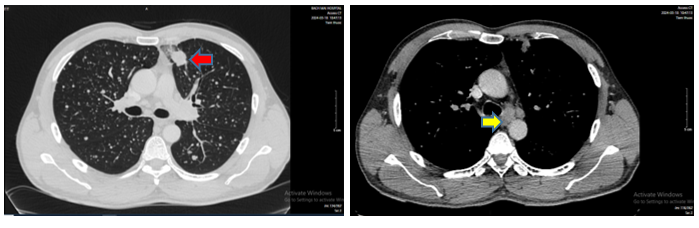

- Chụp cắt lớp vi tính lồng ngực ngày 18/03/2024

Hình 1: Phổi trái nhu mô ngoại vi thùy trên có khối đặc tròn bờ tua gai, kích thước 28x24mm (mũi tên màu đỏ), ngấm thuốc không đồng nhất sau tiêm. Trung thất cân đối, có vài hạch cạnh khí quản và rốn phổi hai bên, hạch lớn kích thước 14x7mm (mũi tên màu vàng)

- Chụp cắt lớp vi tính ổ bụng:

Hình 3: Hình ảnh nhu mô gan sát bao gan phân thùy S5 có nốt giảm tỷ trọng trước tiêm, ngấm thuốc kém sau tiêm, đường kính 10mm (mũi tên đỏ). Tuyến thượng thận trái dày cạnh trong thành các nốt, nốt lớn nhất kích thước 14x25mm ( mũi tên vàng), bờ đều, sau tiêm ngấm thuốc kém.